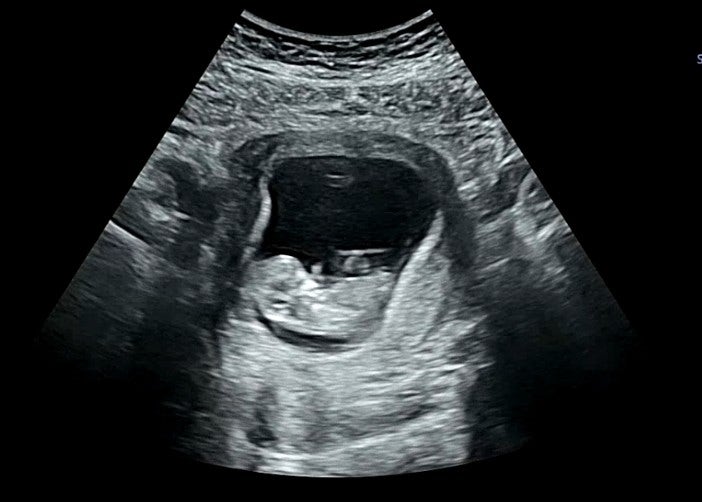

[pregnancy.18] 임신 26주~30주 스토리(임신중기,임신배사진,임산부필라테스,태동,튼살크림,임신중기출혈,육아용품,압타밀분유,화원5일장,입체초음파,대구베이비페어,임신후기)

[pregnancy.8]임신 초기에서 점점 안정이 되어가는13주14주이야기(대구여성아이병원,1차입체초음파,임산부왁싱,보건소임산부교실,뚱채김밥,수박,신마산식당,ici에타,최가네케크)